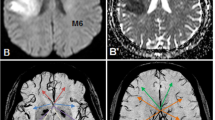

All images were collected from our picture archiving and communication system as DICOM-format data and imported to an Osirix image viewer (Version 3.8.1, 32 bit) on an Apple iMac for analysis. A 10-point semi-quantitative CT scoring system, Alberta Stroke Program Early CT Score (ASPECTS) [14], was used to assess the size abnormal signal intensities or densities on individual DWI, SWI, PWI and FI studies. Two neuroradiologists (H.W.K. and F.Y.T.), blinded to patient information except for the clinical history of ischaemic stroke, independently assessed ASPECTS values on the selected images. For calculating ASPECTS values, 1 point was subtracted from 10 for an area of ischaemic changes, including restricted diffusion, asymmetric prominent vessels on SWI, prolonged MTT, reduced rCBF and rCBV, hyperintensity on FLAIR images and hypointensity on CT (Fig. 1). Image contrast and brightness were optimised between areas of ischaemic changes and normal-appearing brain.

An example of ASPECTS assessment on a 54-year-old woman. Initial MR imaging was performed 7 h after symptom onset. The 10 ASPECTS regions are C caudate, L lentiform nucleus, IC internal capsule, I insular ribbon, M1–6 cortical regions of the middle cerebral artery (M1–3 at the level of basal ganglia, M4–6 at the level rostral to the ganglionic structures). a On diffusion-weighted images, the ASPECTS value is 7 because of hyperintensities in the left I, M2, M5. On b the mean transit time (MTT) map and c susceptibility-weighted images, the ASPECTS values are 3 as areas of prolonged MTT or asymmetric prominent vessels involve I and M1–6. d On follow-up fluid-attenuated inversion recovery images, obtained 47 days after symptom onset, the ASPECTS value is 5 as the hyperintensities involve the I, L, M2, M4 and M5